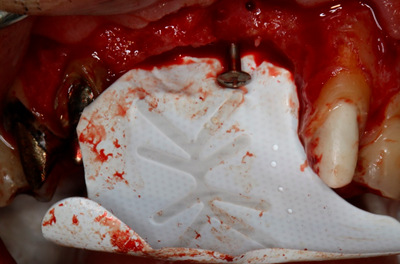

A preservação do alvéolo é uma opção de tratamento, evitando ou reduzindo a perda óssea. Alguns procedimentos são sugeridos com o objetivo de reduzir essa perda fisiológica, como a utilização de biomateriais preenchendo o alvéolo, barreiras, instalação de implante imediato entre outros. 4

Avaliamos o desempenho do biomaterial de hidroxiapatita com colágeno tipo I (Extra Graft XG-13®) na manutenção do volume alveolar.

A aplicação como o caso clínico abaixo se mostrou uma técnica acessível a todos cirurgiões dentistas, pois se trata de um procedimento de simples execução e acessível. Logo, deveria constar na clínica diária.